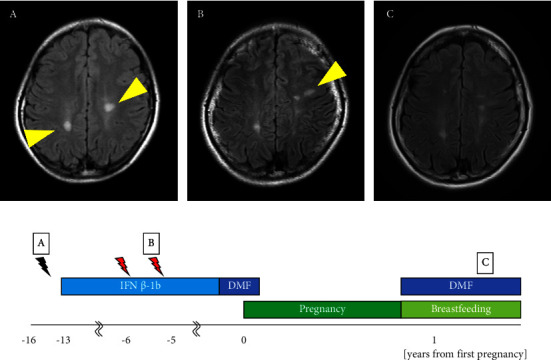

Interferon β and glatiramer acetate are the disease-modifying drugs (DMDs) considered relatively safe for use in pregnant women with multiple sclerosis (MS); however, the safety profile of dimethyl fumarate (DMF) and natalizumab (NTZ) in this population remains inconclusive. Here, we present four cases of pregnant women with MS who were treated with DMF and NTZ (n = 2 patients, each) during their pregnancy and discuss our observations with the use of these drugs and the clinical courses of the patients. We retrospectively examined relapse of MS during pregnancy and after delivery; duration of exposure to DMDs; maternal, fetal, and neonatal adverse events; breastfeeding; and timing of resumption of DMDs. The two patients treated with DMF discontinued treatment 5 or 6 weeks after the discovery of pregnancy. DMF was resumed 1 week postpartum, and mixed breastfeeding was initiated. Brain magnetic resonance imaging in one patient 9 months after delivery revealed a new lesion; however, it was not classified as a clinical relapse. In two patients treated with NTZ, the dosing interval was extended to 6 weeks after the discovery of pregnancy. One patient discontinued NTZ at 30 weeks and the other at 25 weeks of gestation, as a slight restriction in fetal growth was observed owing to hyperemesis gravidarum. Both patients opted for formula feeding, and no relapse was observed within 1 year postpartum. Additionally, no abnormalities were observed in any of the patients during the perinatal period, and their development was normal. Investigation of drug safety in pregnant and parturient women primarily relies on registries, postmarketing surveillance, and case reports due to ethical limitations on conducting randomized controlled trials. Our findings demonstrated that DMF and NTZ were not contraindicated during pregnancy or the perinatal period in women with MS; nevertheless, vigilant monitoring is essential to ensure the safety of these drugs.